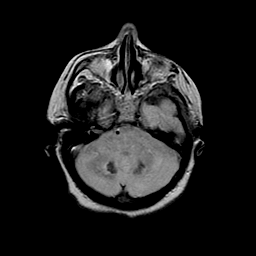

Basal Ganglia Calcification: proton density-weighted MR -- Slice #4

[Home][Help][Clinical] Slice 4